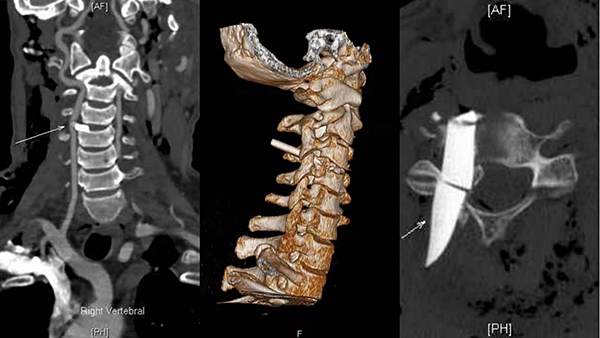

徐醫(yī)附院急診外科值班醫(yī)師姚君偉立刻對(duì)患者進(jìn)行詳細(xì)的查體,發(fā)現(xiàn)患者喉部正中有一長約2cm不規(guī)則傷口,持續(xù)滲血,初步判斷玻璃系從此傷口進(jìn)入頸部,且合并彌漫性氣顱,左耳、額部撕裂傷及右手示指肌腱斷裂。在對(duì)傷口進(jìn)行簡單的消毒包扎及頸托外固定后,立刻對(duì)患者進(jìn)行頸椎三維CT及椎動(dòng)脈CTA檢查。

急診外科主任姚愛明主任醫(yī)師接到病情匯報(bào)后很快抵達(dá)現(xiàn)場,CT結(jié)果令現(xiàn)場所有人大吃一驚:CT顯示玻璃碎片像尖刀一樣刺入頸椎3/4之間,卡在脊髓和椎動(dòng)脈之間。此處脊髓位置較高,一旦損傷輕則癱瘓,重則隨時(shí)心跳呼吸驟停而亡,彌漫性氣顱提示硬膜已經(jīng)破裂!CTA顯示椎動(dòng)脈被明顯壓迫,隨時(shí)可能破裂出血,導(dǎo)致失血性休克、大面積缺血性腦梗死,腦疝甚至死亡!且殘留玻璃碎片中間斷裂破碎,可能無法完全取出,給手術(shù)增加了極大的難度!